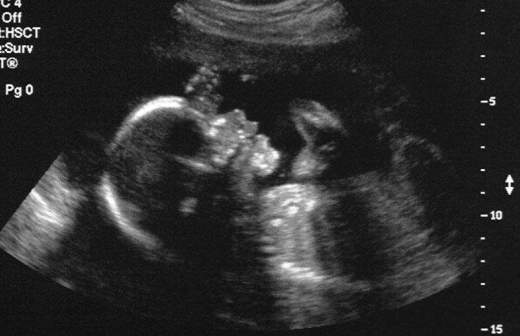

Жительница Ростова-на-Дону требовала, чтобы петербургская клиника, где она проходила первую (неудачную) процедуру, провела ее повторно. И в клинике хранились замороженные эмбрионы, полученные методом интрацитоплазматической инъекции сперматозоида в яйцеклетку (ИКСИ).